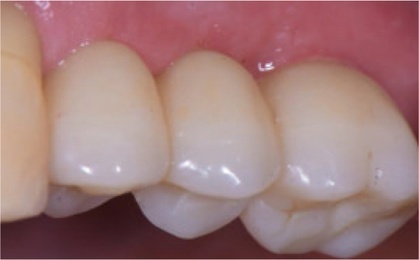

Bild 7:

Vestibuläre Ansicht

Bild  11:

Einzelzahnimplantat in Position 15.